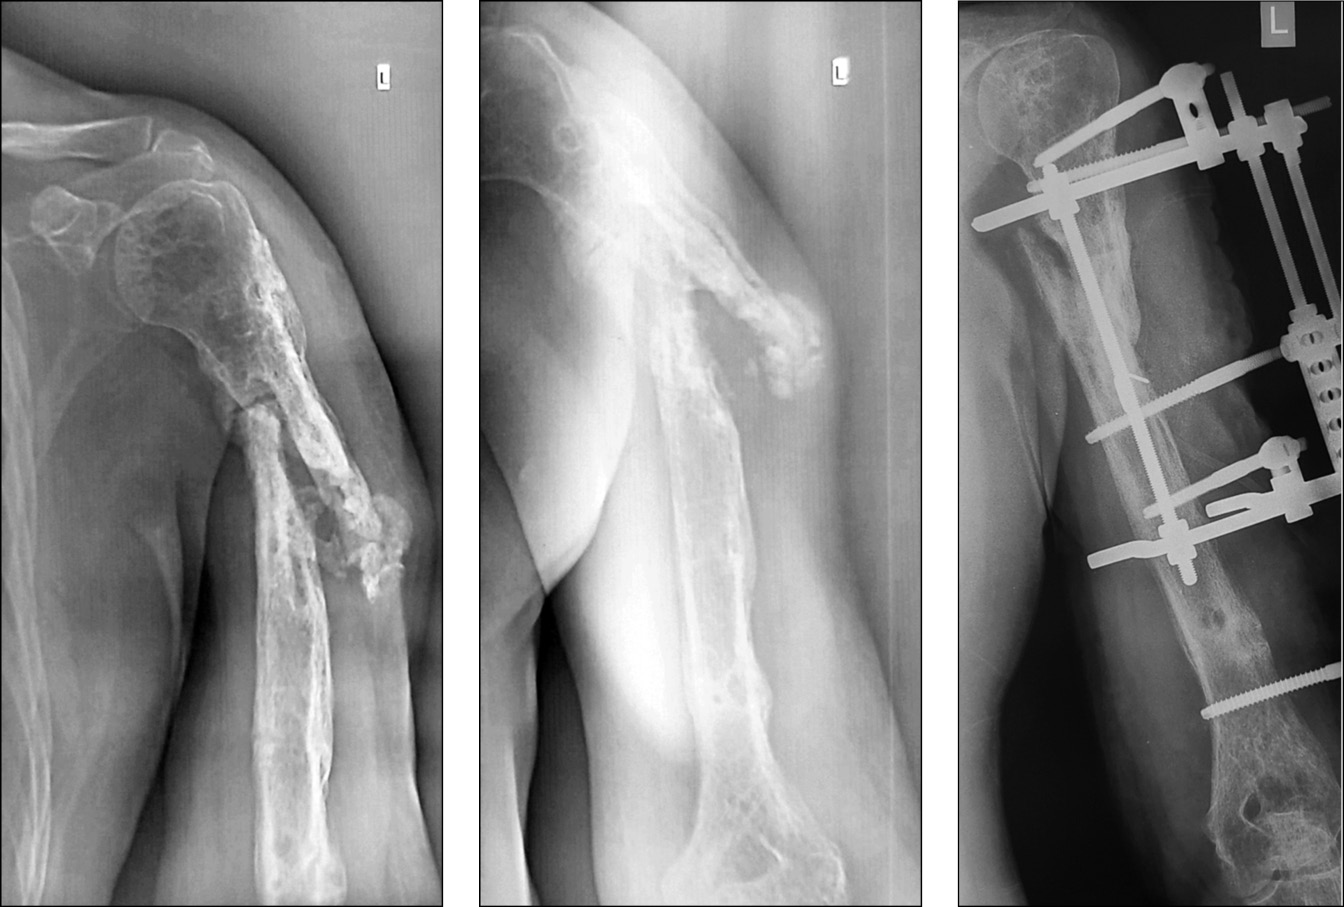

Пациент, 49 лет, получил производственную травму в результате падения с высоты около 2 м. Диагноз: «Закрытый перелом на границе верхней и средней трети левой плечевой кости». Через 5 дней после травмы выполнен остеосинтез пластиной и винтами. Спустя месяц открылся свищ, в связи с чем произведено удаление металлоконструкции, секвестрнекрэктомия и реостеосинтез левой плечевой кости аппаратом внешней фиксации. Аппарат демонтирован через 6 мес. В последующем выполнялись неоднократные санационные операции левой плечевой кости по поводу рецидива в разных лечебных учреждениях (рис. 5).

Рис. 5. Послеоперационные рентгенограммы левой плечевой кости после секвестрнекрэктомии

Через 5 мес. при повторном падении пациент получил патологический перелом на границе проксимального и среднего отдела диафиза левой плечевой кости (рис. 6). Госпитализирован в нашу клинику.

Рис. 6. Рентгенограммы левой плечевой кости при поступлении пациента в наше отделение

В условиях нашей клиники выполнена операция: 1. Экономная резекционная секвестрнекрэктомия левой плечевой кости. 2. Реостеосинтез левой плечевой кости аппаратом внешней фиксации стержневой компоновки (рис. 7).

Рис. 7. Рентгенограммы левой плечевой кости после операции

Резекция костной ткани осуществлена в пределах жизнеспособной ткани. Согласно критериям биомеханической концепции, двухрычаговый перелом зафиксирован на 4 уровнях фиксации, по 2 уровня на каждом отломке. Рана была дренирована. В послеоперационном периоде проведена антибактериальная терапия [с учетом данных микробиологического исследования — метициллинрезистентный золотистый стафилококк (MRSA)]: Ванкомицин по 1 г 2 раза в день в/в капельно 12 дней. Параллельно проводили противовоспалительную, инфузионную терапию. Послеоперационная рана зажила первичным натяжением. Дренажная трубка удалена на третьи сутки.